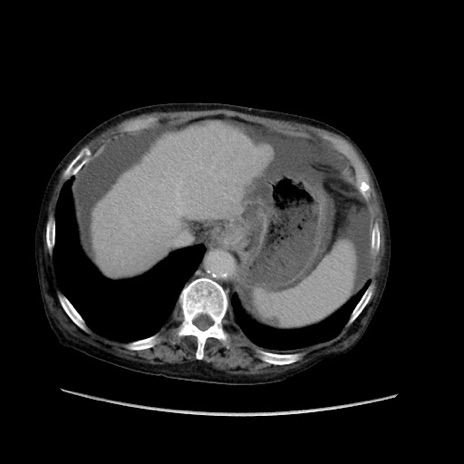

症例31(横断像)

【症例】80歳代 女性

【主訴】腹部膨満感

【現病歴】他院にて肝硬変にてフォロー中。1週間前から便秘、腹部膨満感、臍部腫瘤あり受診となる。

【既往歴】肝硬変

【身体所見】腹部膨隆あり、皮膚変化なし、疼痛なし。

【データ】WBC 4600、CRP 0.25